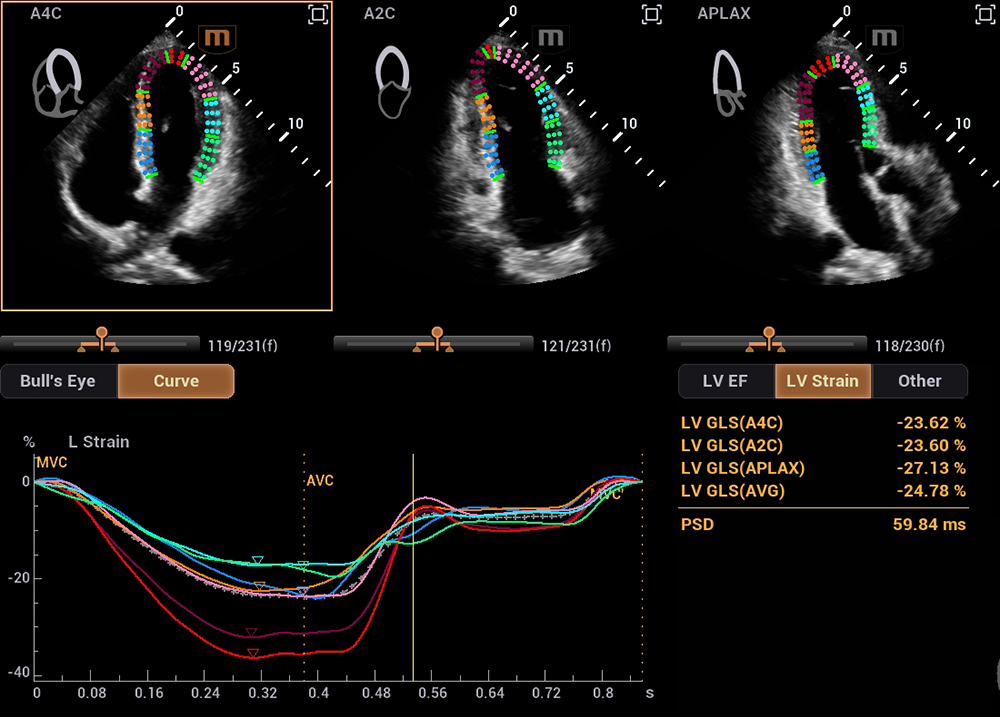

在研发中,迈瑞研发团队另辟蹊径,推出了自动左心室应变评估 Auto Strain LV 。该功能不再依赖心电信号作为“时间坐标”,而是让 AI 直接识别心脏机械运动的关键节点——当二尖瓣关闭、主动脉瓣开放,这些瓣膜运动的瞬间,就是心脏收缩与舒张的自然锚点。

自动左心室应变评估 Auto Strain LV(非心电触发)

同时,这项技术的数据直接源于机械运动的时相判定,没有电信号干扰与延迟误差,更真实地反映心脏“做了什么”。有效避免了心律失常、起搏器植入、幼儿及急诊术中等场景下,心电信号出现缺失、干扰的影响。